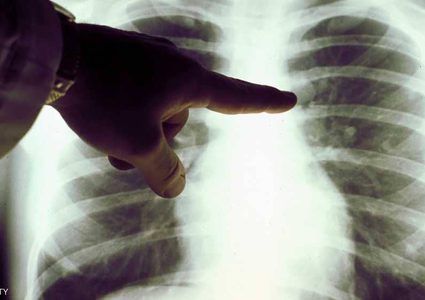

يعتبر سرطان الرئة أحد أكثر اسباب الوفاة شيوعا بين الرجال والنساء في الولايات المتحدة الامريكية، حسب جمعية السرطان الامريكية. حيث وجدت دراسة جديدة ان الفلفل …

يرتبط سرطان الرئة بشكل وثيق مع التدخين، ولكن نسبة الإصابة به ارتفعت بشكل ملحوظ بين أوساط النساء، بينما تتراجع سنويا عند الرجال. وتزداد أعداد النساء المصابات …

أظهرت نتائج أولية أن فحص دم تجريبيا تطوره شركة جريل يبشر باكتشاف سرطان الرئة في مراحله المبكرة استناداً إلى الحمض النووي العائم الذي يطلقه الورم في الدم. …

قبل الإقدام على خطوة تلقي علاج سرطان الرئة، يحدد الأطباء بعد التشخيص العلاج الآمن والفعال حسب كل حالة ومراحل تقدم المرض. ووفقاً لموقع " cancer" المتخصص …